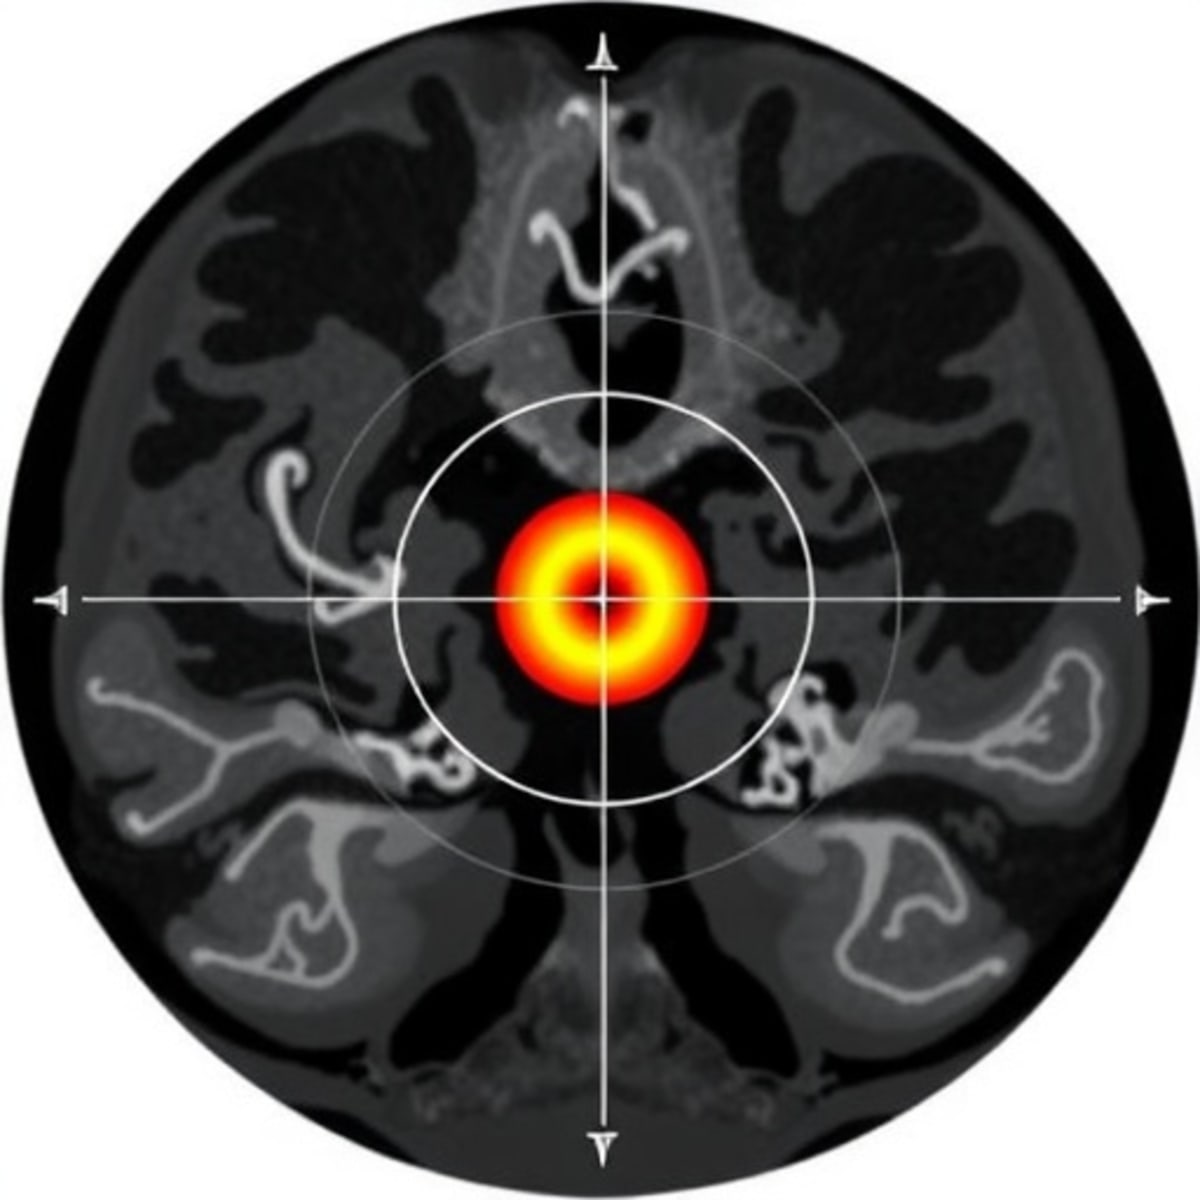

Professor Maria Sunnerhagen's team used a clever combination of advanced imaging, artificial intelligence, and biochemical testing to map exactly where N-MYC connects with another cancer protein called Aurora A. By understanding this handshake between the two proteins, they found a way to break them apart.